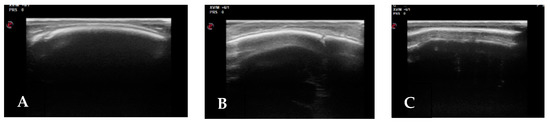

- Marino, S.; Martino, R.; Marino, L.; Falsaperla, R. Sutures ultrasound: Useful diagnostic screening for posterior plagiocephaly. Child Nerv. Syst. 2021, in press. [Google Scholar]